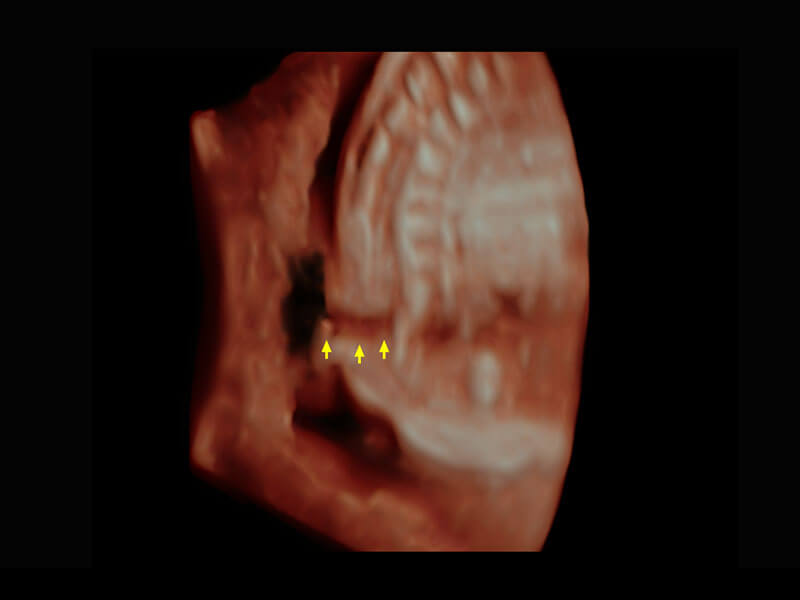

P60提供简单易学易用的高端诊断工具,为您中晚孕筛查提供快速清晰的解剖信息。

S-Fetus能够助您在实时扫查过程中自动识别标准切面、自动测量并录入报告。一个按键,即可快速、高效地获取胎儿生理指标,简化您的产科检查操作。